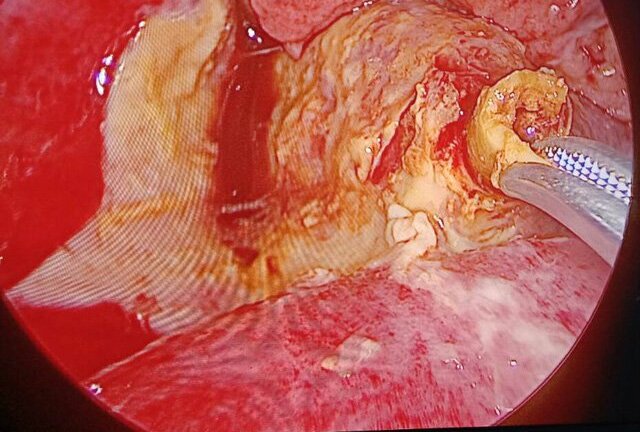

Một bệnh nhân bị thủng ruột non, gây nhiều dịch mủ trong ổ bụng do nuốt phải xương gà được Bệnh viện Xanh pôn cứu sống.